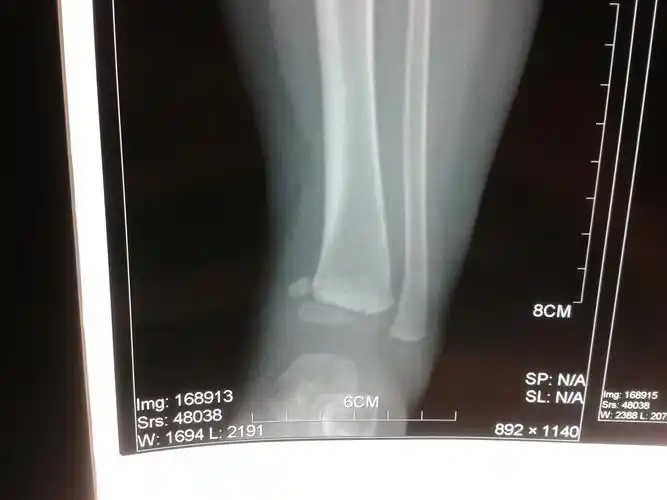

小儿胫骨远端干骺端骨折伴骨骺滑脱

胫骨干骺端骨折

12岁儿童胫骨远端三平面骨骺骨折

左胫骨骨骺骨折